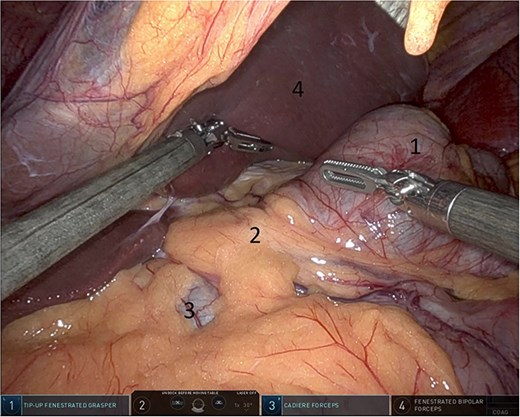

Upon entering the abdominal cavity, dilated bowel loops were observed (Fig. 2), and a significant portion of the colon was found herniated through the foramen of Winslow (Fig. 3). The herniated colon was covered by the pars flaccida (Fig. 4) (Video S1). Careful dissection was performed anterior to the hepatoduodenal ligament (Fig. 5). The gall bladder was retracted to the patient's right upper quadrant, which allowed for the retraction of the foramen of Winslow (Fig. 6) (Video S1). After carefully placing the tip of the instrument posterior to the portal vein and gently elevating it, the herniated colon was successfully reduced (Fig. 7) (Video S1).

Dissection anterior to the hepatoduodenal ligament (1: portal vein, 2: foramen of Winslow, 3:first part of the duodenum).